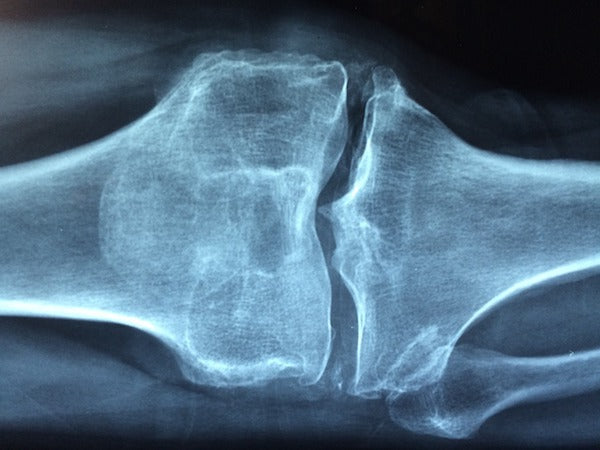

Medications in the category of bisphosphonates are the most common medications prescribed for osteoporosis. After 5 years of ingesting these medications, a small percentage of people are experiencing more, not less, fractures.

These fractures occur with little or no trauma.

This is pointing to poor bone quality – in other words, these medications may build some bone, but after 5 years of taking them the bones may become more fragile in some people.

If you have low bone density, that will impact your bone quality. However, you can have good bone density and poor bone quality. Many things impact bone quality including digestive health, nutritional factors, smoking cigarettes and many other lifestyle and hereditary factors.

There are cases where people have a good bone density yet experience a fragility fracture that may indicate poor bone quality.